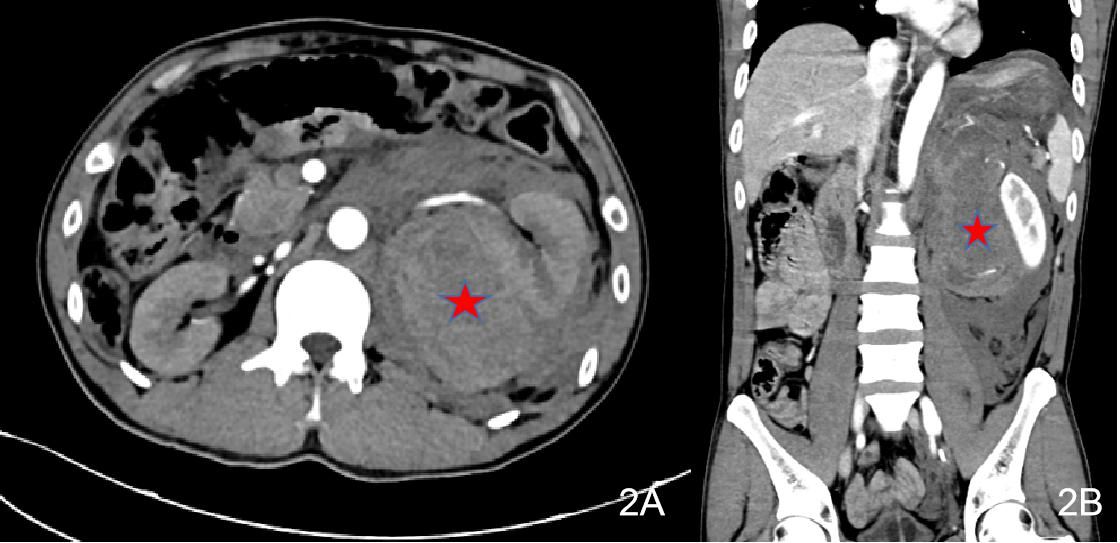

辅助检查如下。2021-06-17本院急诊生化十项:K 3.75 mmol/L,Ca 1.98 mmol/L,CR 116.6 μmol/L,GLUC 30.28 mmol/L;血清肌钙蛋白Ⅰ测定:TnI 21.645 ng/mL;凝血机制六项组合:Fib 1.25 g/L,APTT 21.5 s,DDi 2.97 mg/L;腹部CT平扫+ 增强(见图 2)。左侧肾上腺区占位,考虑肿瘤伴破裂出血,左侧腹膜后、腹盆腔广泛积血,拟左肾上腺来源可能。双下肺渗出,左侧少量胸腔积液,双下肺局部肺不张。右肾小囊肿。2021-06-17常规心电图检查:窦性心动过速非特异性室内传导阻滞T波异常(Ⅰ aVL V5 V6导联低平、浅倒)。

图 2 2021-06-17患者2腹部CT(左侧肾上腺占位伴出血)